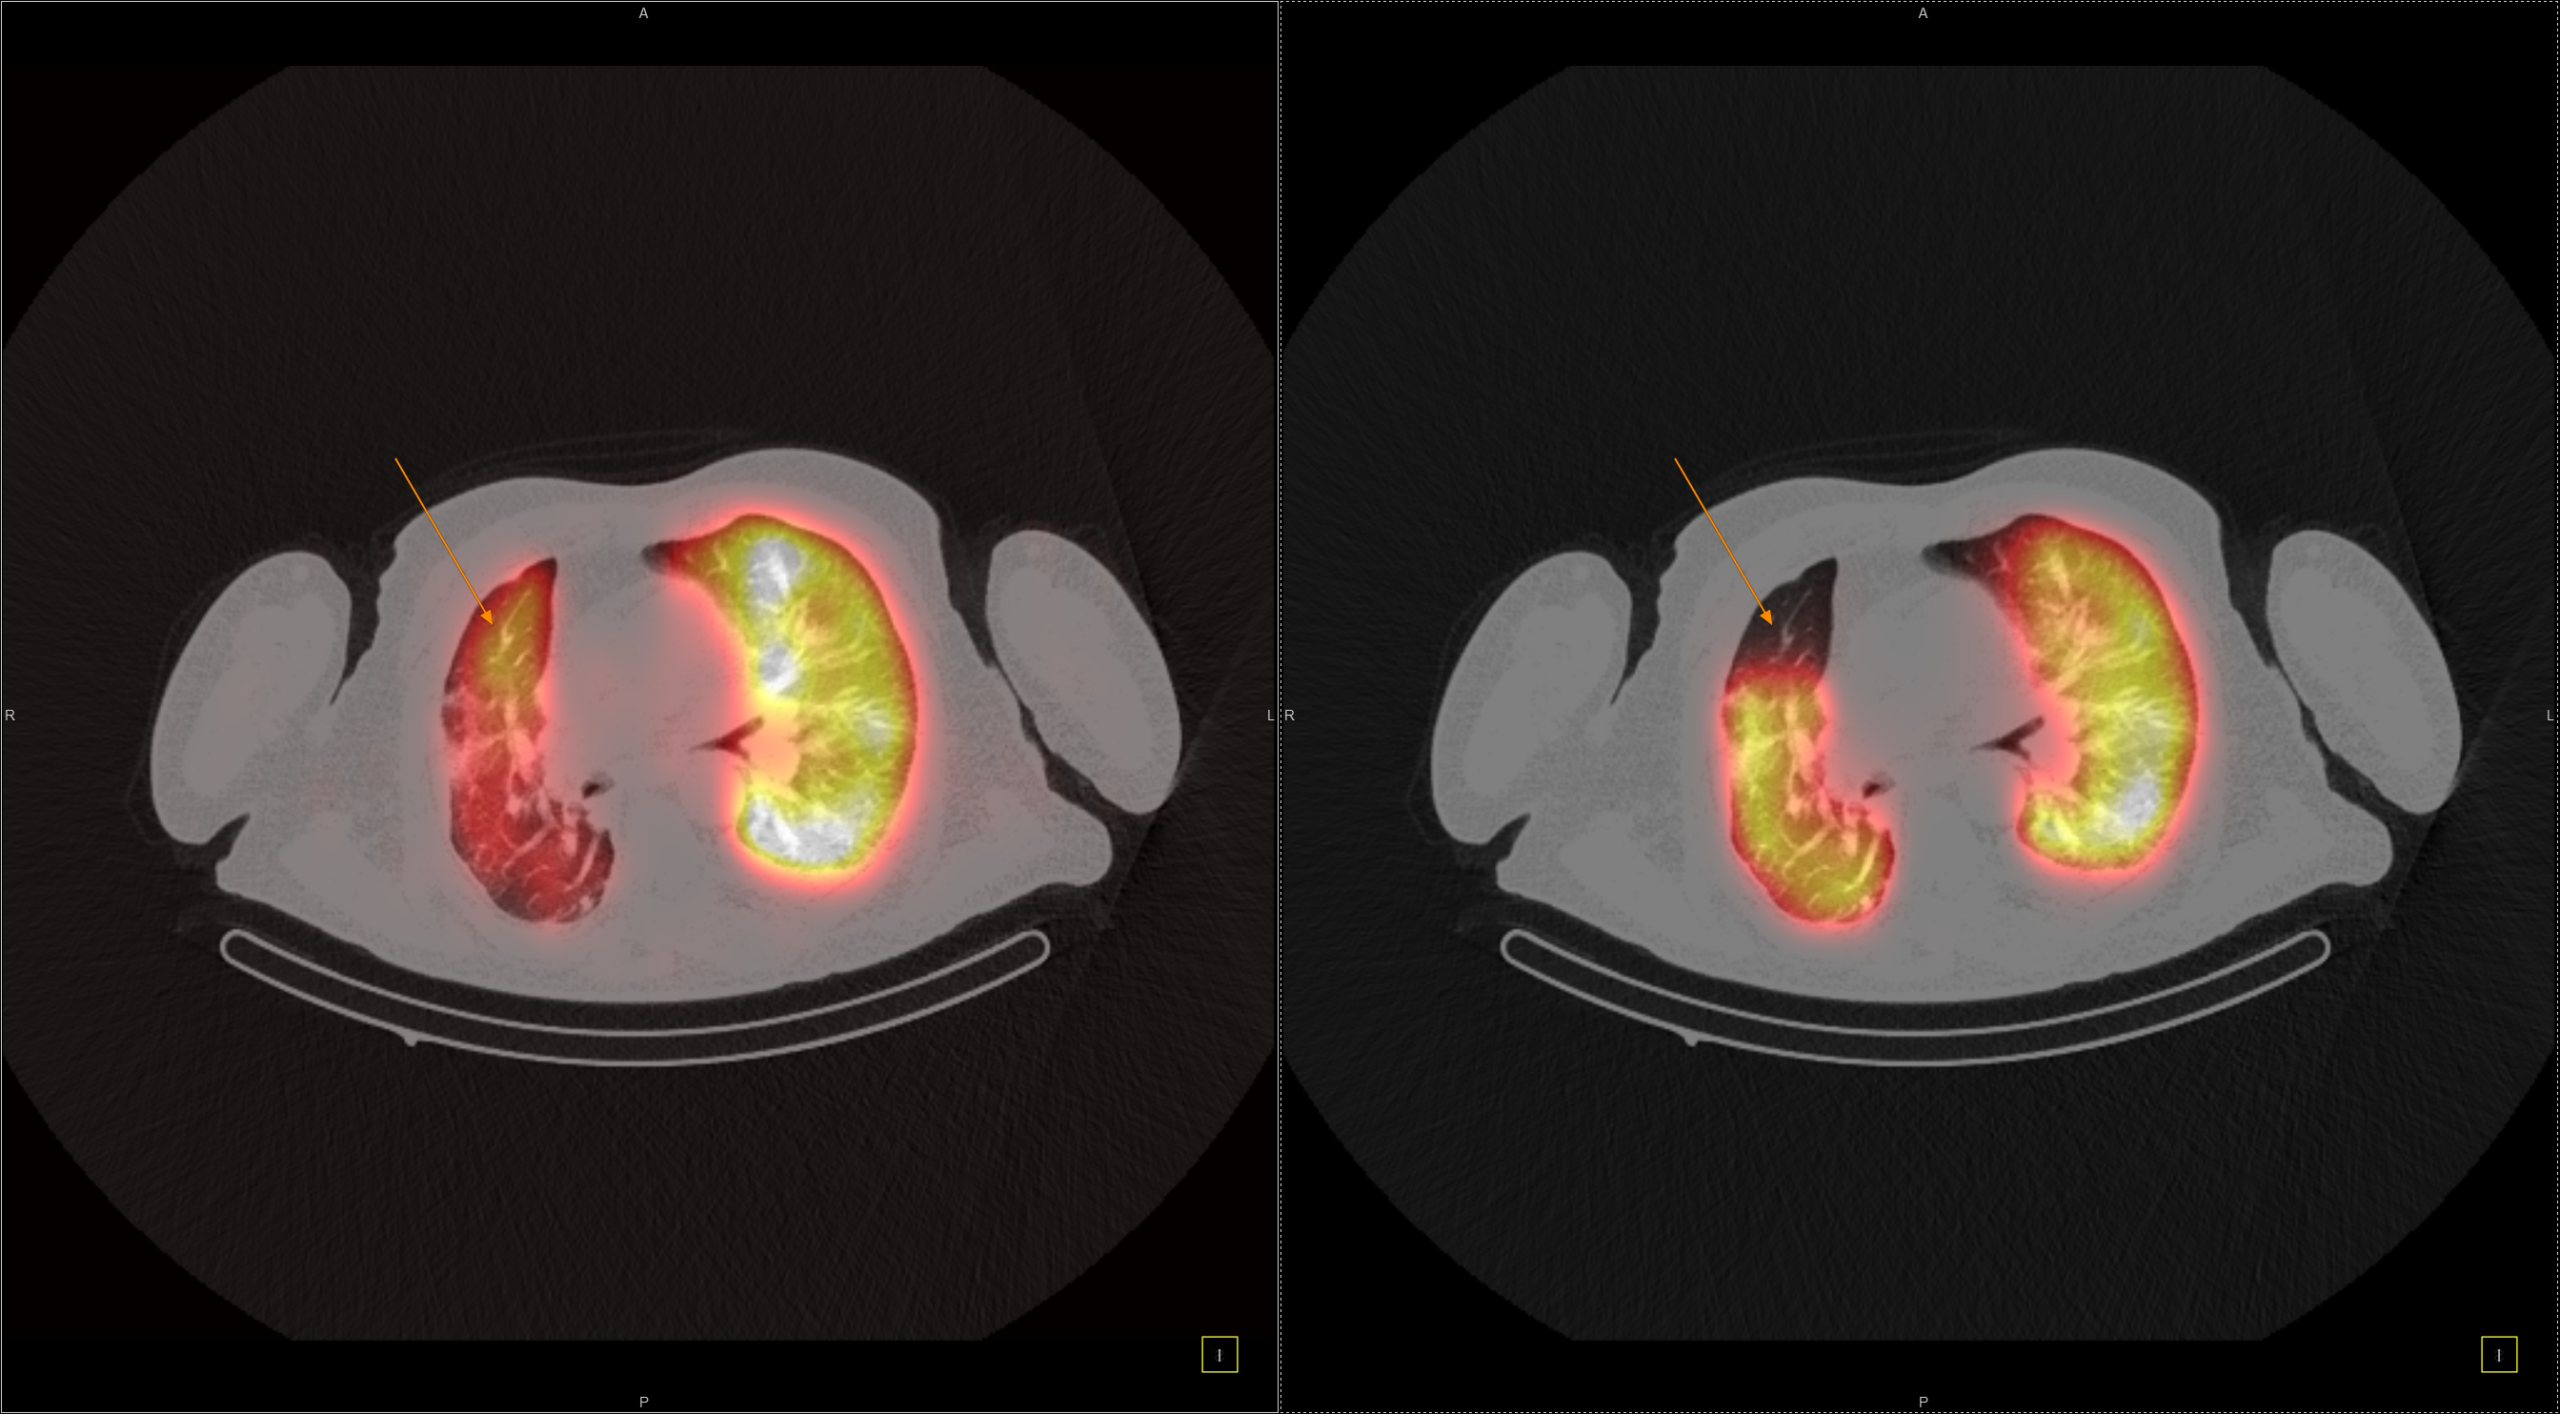

IQ SPECT Η τέχνη της ελαχιστοποίησης της δόσης με ταυτόχρονη μεγιστοποίηση της ταχύτητας Στη σύγχρονη Πυρηνική Ιατρική, όπου η ανάγκη για ταχύτερες και ασφαλέστερες μελέτες Μυοκαρδιακής Αιμάτωσης (MPI) αυξάνεται διαρκώς, το IQ SPECT αποτελεί μία από τις πλέον ώριμες και καινοτόμες τεχνολογίες. Η αρχή του είναι απλή και καθαρή: να συλλέγει όσο το δυνατόν περισσότερα δεδομένα από την καρδιά, με την ελάχιστη δυνατή δόση και στον ελάχιστο χρόνο, χωρίς συμβιβασμούς στην ποιότητα εικόνας. Minimum dose & maximum speed Στις συμβατικές SPECT καρδιάς, μεγάλο τμήμα του ανιχνευτή δεν αξιοποιείται λόγω του μικρού μεγέθους του εξεταζόμενου οργάνου. Αυτό οδηγεί σε παρατεταμένο acquisition – πολλές φορές έως 16 λεπτά – ώστε να εξασφαλιστεί η αναγκαία ποιότητα εικόνας. Το IQ SPECT υπερβαίνει αυτόν τον περιορισμό. Με βελτιστοποιημένο χειρισμό της γεωμετρίας, των collimators και του acquisition, μεγιστοποιεί τα ανιχνευόμενα δεδομένα από την καρδιά, επιτρέποντας ολοκληρωμένη μελέτη σε λιγότερο από 5 λεπτά, μείωση της χορηγούμενης δόσης έως και 75%, και διατήρηση ή και βελτίωση της ποιότητας εικόνας.

Οι μελέτες μυοκαρδίου πραγματοποιούνται με τη χρήση της μοναδικής τεχνολογίας IQ SPECT που εξασφαλίζει μικρό χρόνο απεικόνισης – μικρή δόση – υψηλή διακριτική ικανότητα/ανάλυση.